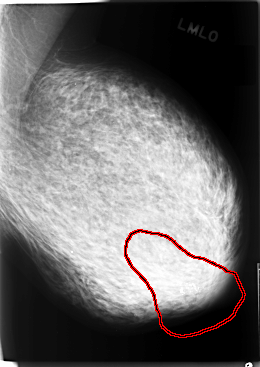

C_0078_1.LEFT_MLO

FILE: C_0078_1.LEFT_MLO.OVERLAY

TOTAL_ABNORMALITIES 1

ABNORMALITY 1

LESION_TYPE CALCIFICATION TYPE PLEOMORPHIC DISTRIBUTION CLUSTERED

ASSESSMENT 5

SUBTLETY 5

PATHOLOGY MALIGNANT

TOTAL_OUTLINES 1

BOUNDARY